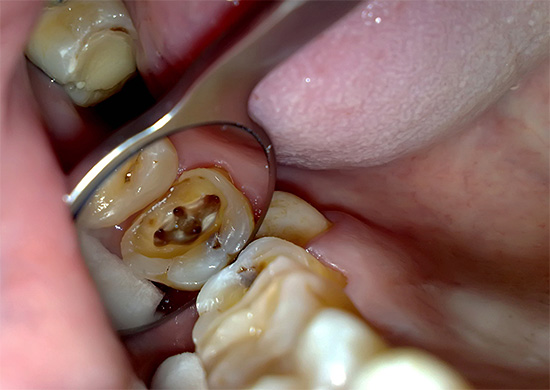

pulpite È una malattia in cui si verifica l'infiammazione del cosiddetto "nervo" dentale (polpa). I molari grandi (molari) hanno spesso tre canali, in ciascuno dei quali è presente un fascio neurovascolare. Quando si verifica un processo infiammatorio nella polpa, si gonfia e si stringe, a seguito del quale una persona può sentire un forte dolore.

Oggi, nella maggior parte delle cliniche, la pulpite a tre canali è quasi sempre trattata dall'estirpazione - estrazione nervosa da tutti i canali e il loro riempimento nella fase finale del trattamento intracanal.